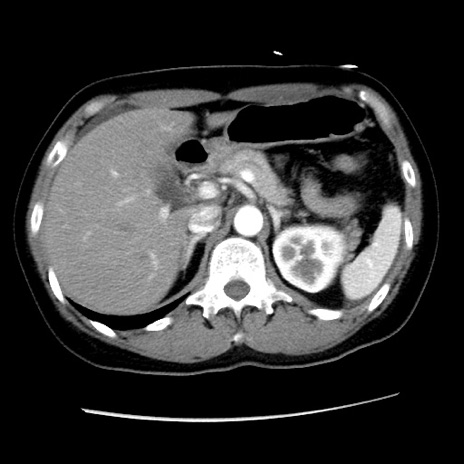

症例10(横断像)

【症例】 50歳代女性

【主訴】 腹痛

【現病歴】前日生レバーを食べた。今朝に排便あり。 昼前に突然発症の腹痛を生じ、当院救急外来を受診した。

【身体所見】 意識清明、腹部:平坦、軟、下腹部やや左を中心に圧痛・反跳痛あり、筋性防御あり

【データ】WBC 7800、CRP 0.07